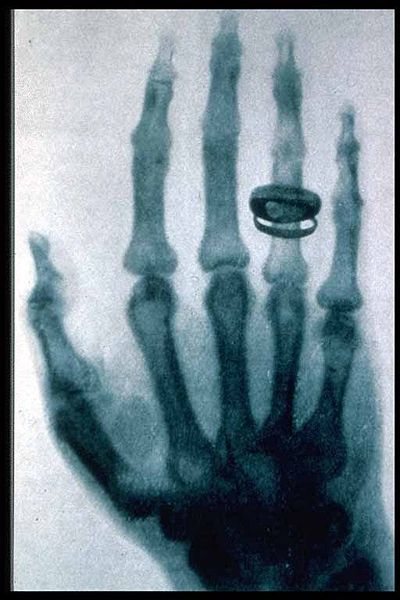

X ışınlanndan ilk olarak tıpta yararlanılmıştır. Tıpta X ışınlan tanı ya da tedavi amacıyla kullanılır. Tanı amacıyla kemik kınklannın, vücutta yabancı maddelerin, diş çürüklerinin, kanser ve benzeri hastalıklı durumların belirlenmesinde yararlanılan X ışınlan, tedavi amacıyla da özellikle kötü huylu (habis) urların yayılmasının engellenmesinde kullanılır.